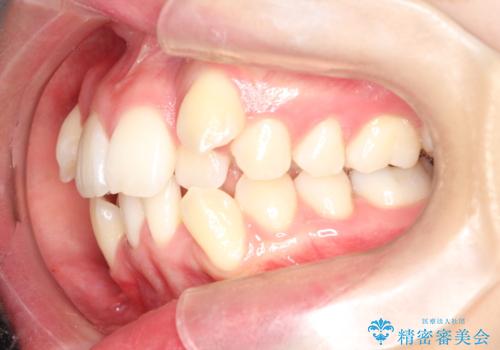

重度のガタガタ ハーフリンガルによる目立たない抜歯矯正

- 八重歯と前歯のガタガタを主訴に来院されました。

目立たない装置をご希望でしたので、上下左右の歯を1本ずつ抜歯してハーフリンガルでの矯正を行いました。

歯並びがコンプレックスで歯を見せて笑うことができなかったとのことですが、歯並びがよくなり、口元を気にせずに笑えるようになったと喜んでいただきました。